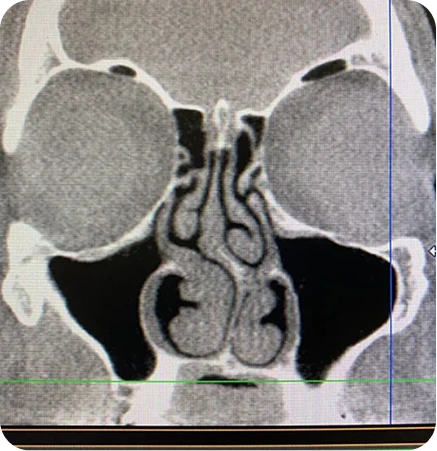

For example, swelling from chronic sinusitis, a deviated septum, enlarged turbinates, and nasal valve collapse could all be the cause. Fixing one of these things, but not the others, will not correct the problem. In this case, the answer would be balloon sinuplasty to fix the sinusitis, turbinate reduction, septoplasty, and nasal valve reconstruction.

At our Houston clinic, we take a personalized approach to diagnosing and treating nasal congestion, difficulty breathing, and other sinus conditions. Using advanced tools like the NOSE score test and nasal endoscopy, we carefully evaluate both nostrils to identify the underlying cause of your symptoms, whether it’s turbinate hypertrophy, nasal polyps, a deviated septum, or chronic sinusitis. Our team also assesses how structural issues or inflammation may pull outward on nasal passages, contributing to trouble sleeping, sinus pressure, or other symptoms.